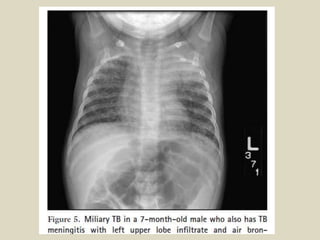

Criterios Radiológicos

diagnóstico

• Edad: 1 año 9 meses

• Tos desde hace 1 año

• Diaforesis

• Falta de apetito

• Ex físico: normal

• Multiples tratamientos

• Peso al inicio: 9 Kg

• Peso a los 2 meses: 12

Kg